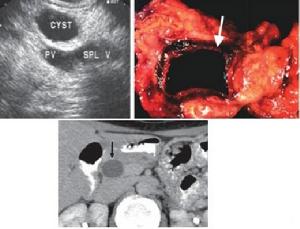

3.B型超聲檢查:

可以顯示腫瘤的部位、大小及其與周圍器官之間的關係,有助於明確胰腺腫塊的囊、實性,囊腔的大小和多寡,囊內容物、囊壁及其間隔等的結構和形態的特徵,為診斷與鑑別診斷提供重要依據。